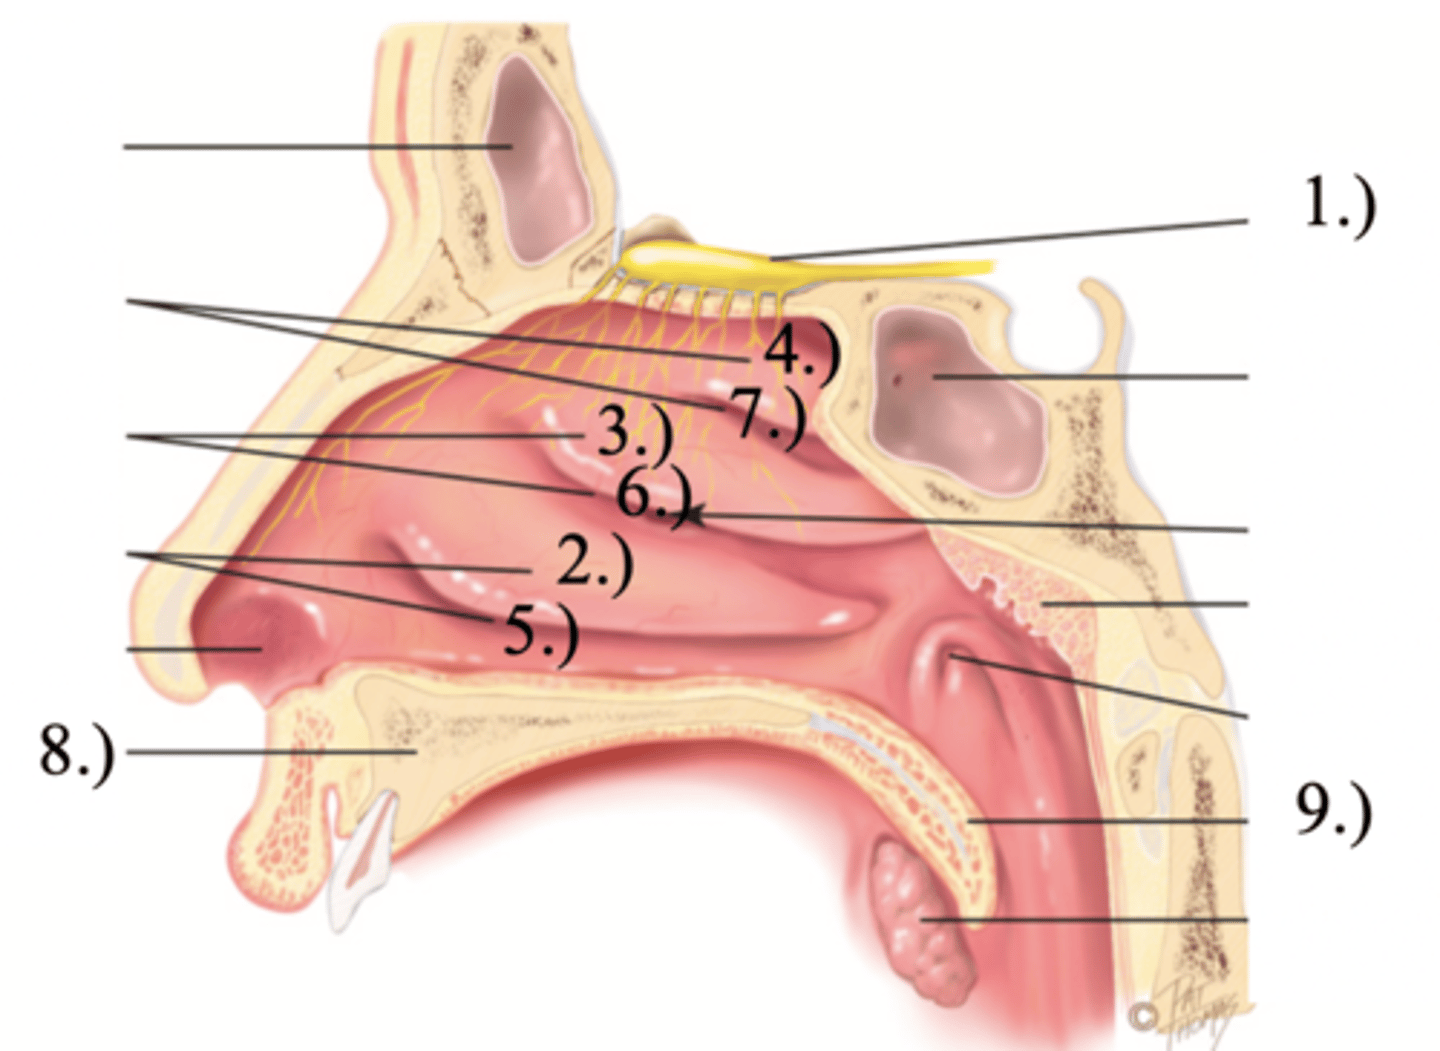

Turbinates (Conchae)

- There's an inferior, middle, and superior one (2.), 3.), 4.))

Olfactory Region

A dime-sized area at the top of each nasal cavity that houses sensors responsible for smell (1.))

Meatuses

- There's an inferior, middle, and superior one

(5.), 6.), 7.))

Anterior palate portion that is supported by the palatine processes of the maxillae and the palatine bones (8.))

Posterior palate portion, not supported by bone (9.))